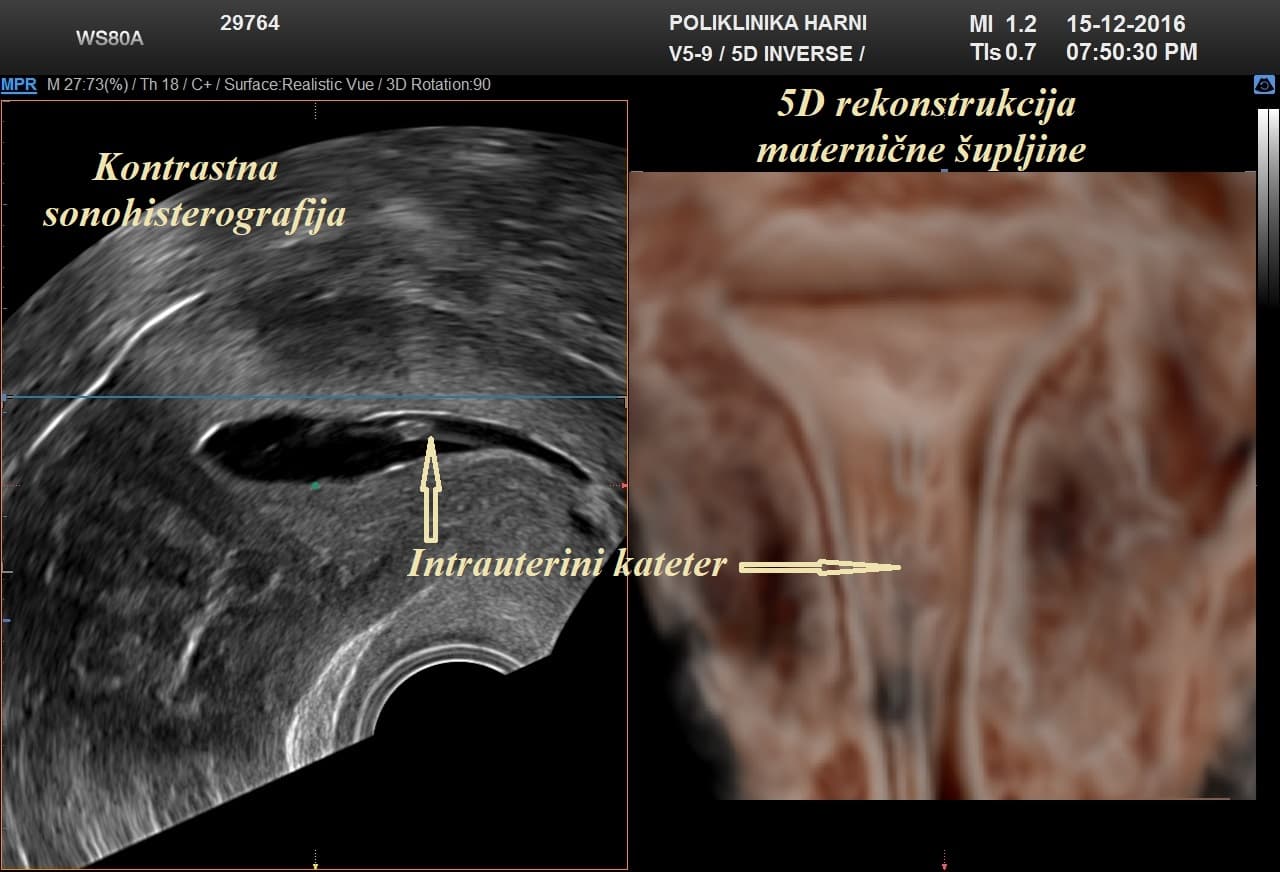

Kontrastni ultrazvukobojenim doplerom i 3D ultrazvukom / Hy-Co-Sy - hysterosalpingo-contrast-sonography sigurna je i učinkovita dijagnostička metoda u procjeni prohodnih jajovoda i od presudnog značenja u obradi neplodnih pacijentica. Provodi se u prvom dijelu menstruacijskog ciklusa nakon potpunog prestanka menstruacijskog krvarenja. Nakon pripreme pacijentice, u kanal vrata maternice se uvodi kateter i ubrizgava kontrast, a potom se prikazuju maternična šupljina, strukture unutar nje, eventualne anomalije maternice i prohodnost jajovoda. Kontraindikacije su trudnoća, krvarenje, akutna zdjelična upala i adneksalni tumor.

Pojava više-dimenzionalnog ultrazvuka omogućuje vizualizaciju ne samo određenih dijelova uterusa nedostupnih dvodimenzionalnom prikazu uslijed položaja uterusa, već i odabir optimalne ravnine kao i načina prikaza sumnjive lezije, a kod 5D ultrazvuka tehnološke inovacije omogućuju dodatne automatske presjeke koji omogućuju slojevitiju sliku i daju dubinu slici ujedno poboljšavajući dijagnostičku točnost. U dijagnostici anomalija uterusa trodimenzionalna rekonstrukcija ima prednost nad dvodimenzionalnim prikazom, te se njegova točnost može mjeriti s točnošću histerosalpingografije.

5D ultrazvučna tehnologija označuje dodatnu, vrhunsku kvalitetu revolucionarnog ultrazvučnog sustava uz automatizaciju tehnike koja više nije apsolutno ovisna o ultrasoničaru, uz najveću kvalitetu dijagnostičkog prikaza na LED monitoru i optimiziranim softverom, koji omogućuje novu slojevitu, dubinsku sliku poput CT prikaza u stvarnoj trećoj dimenziji u svim otvorenim pitanjima kako u ginekologiji, tako i opstetriciji.